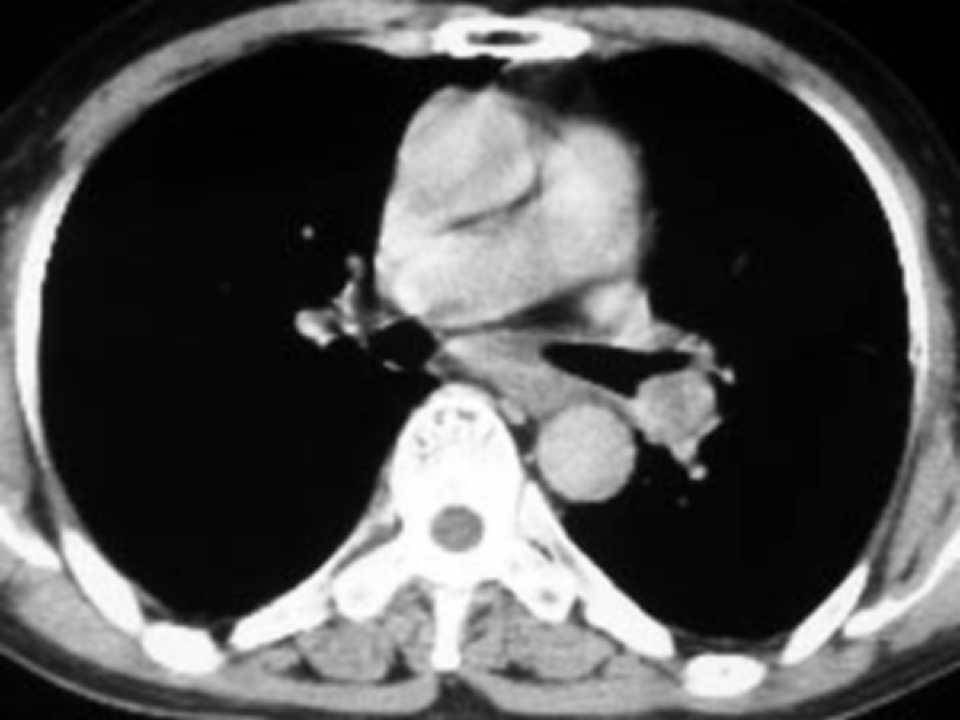

肺癌影像学表现